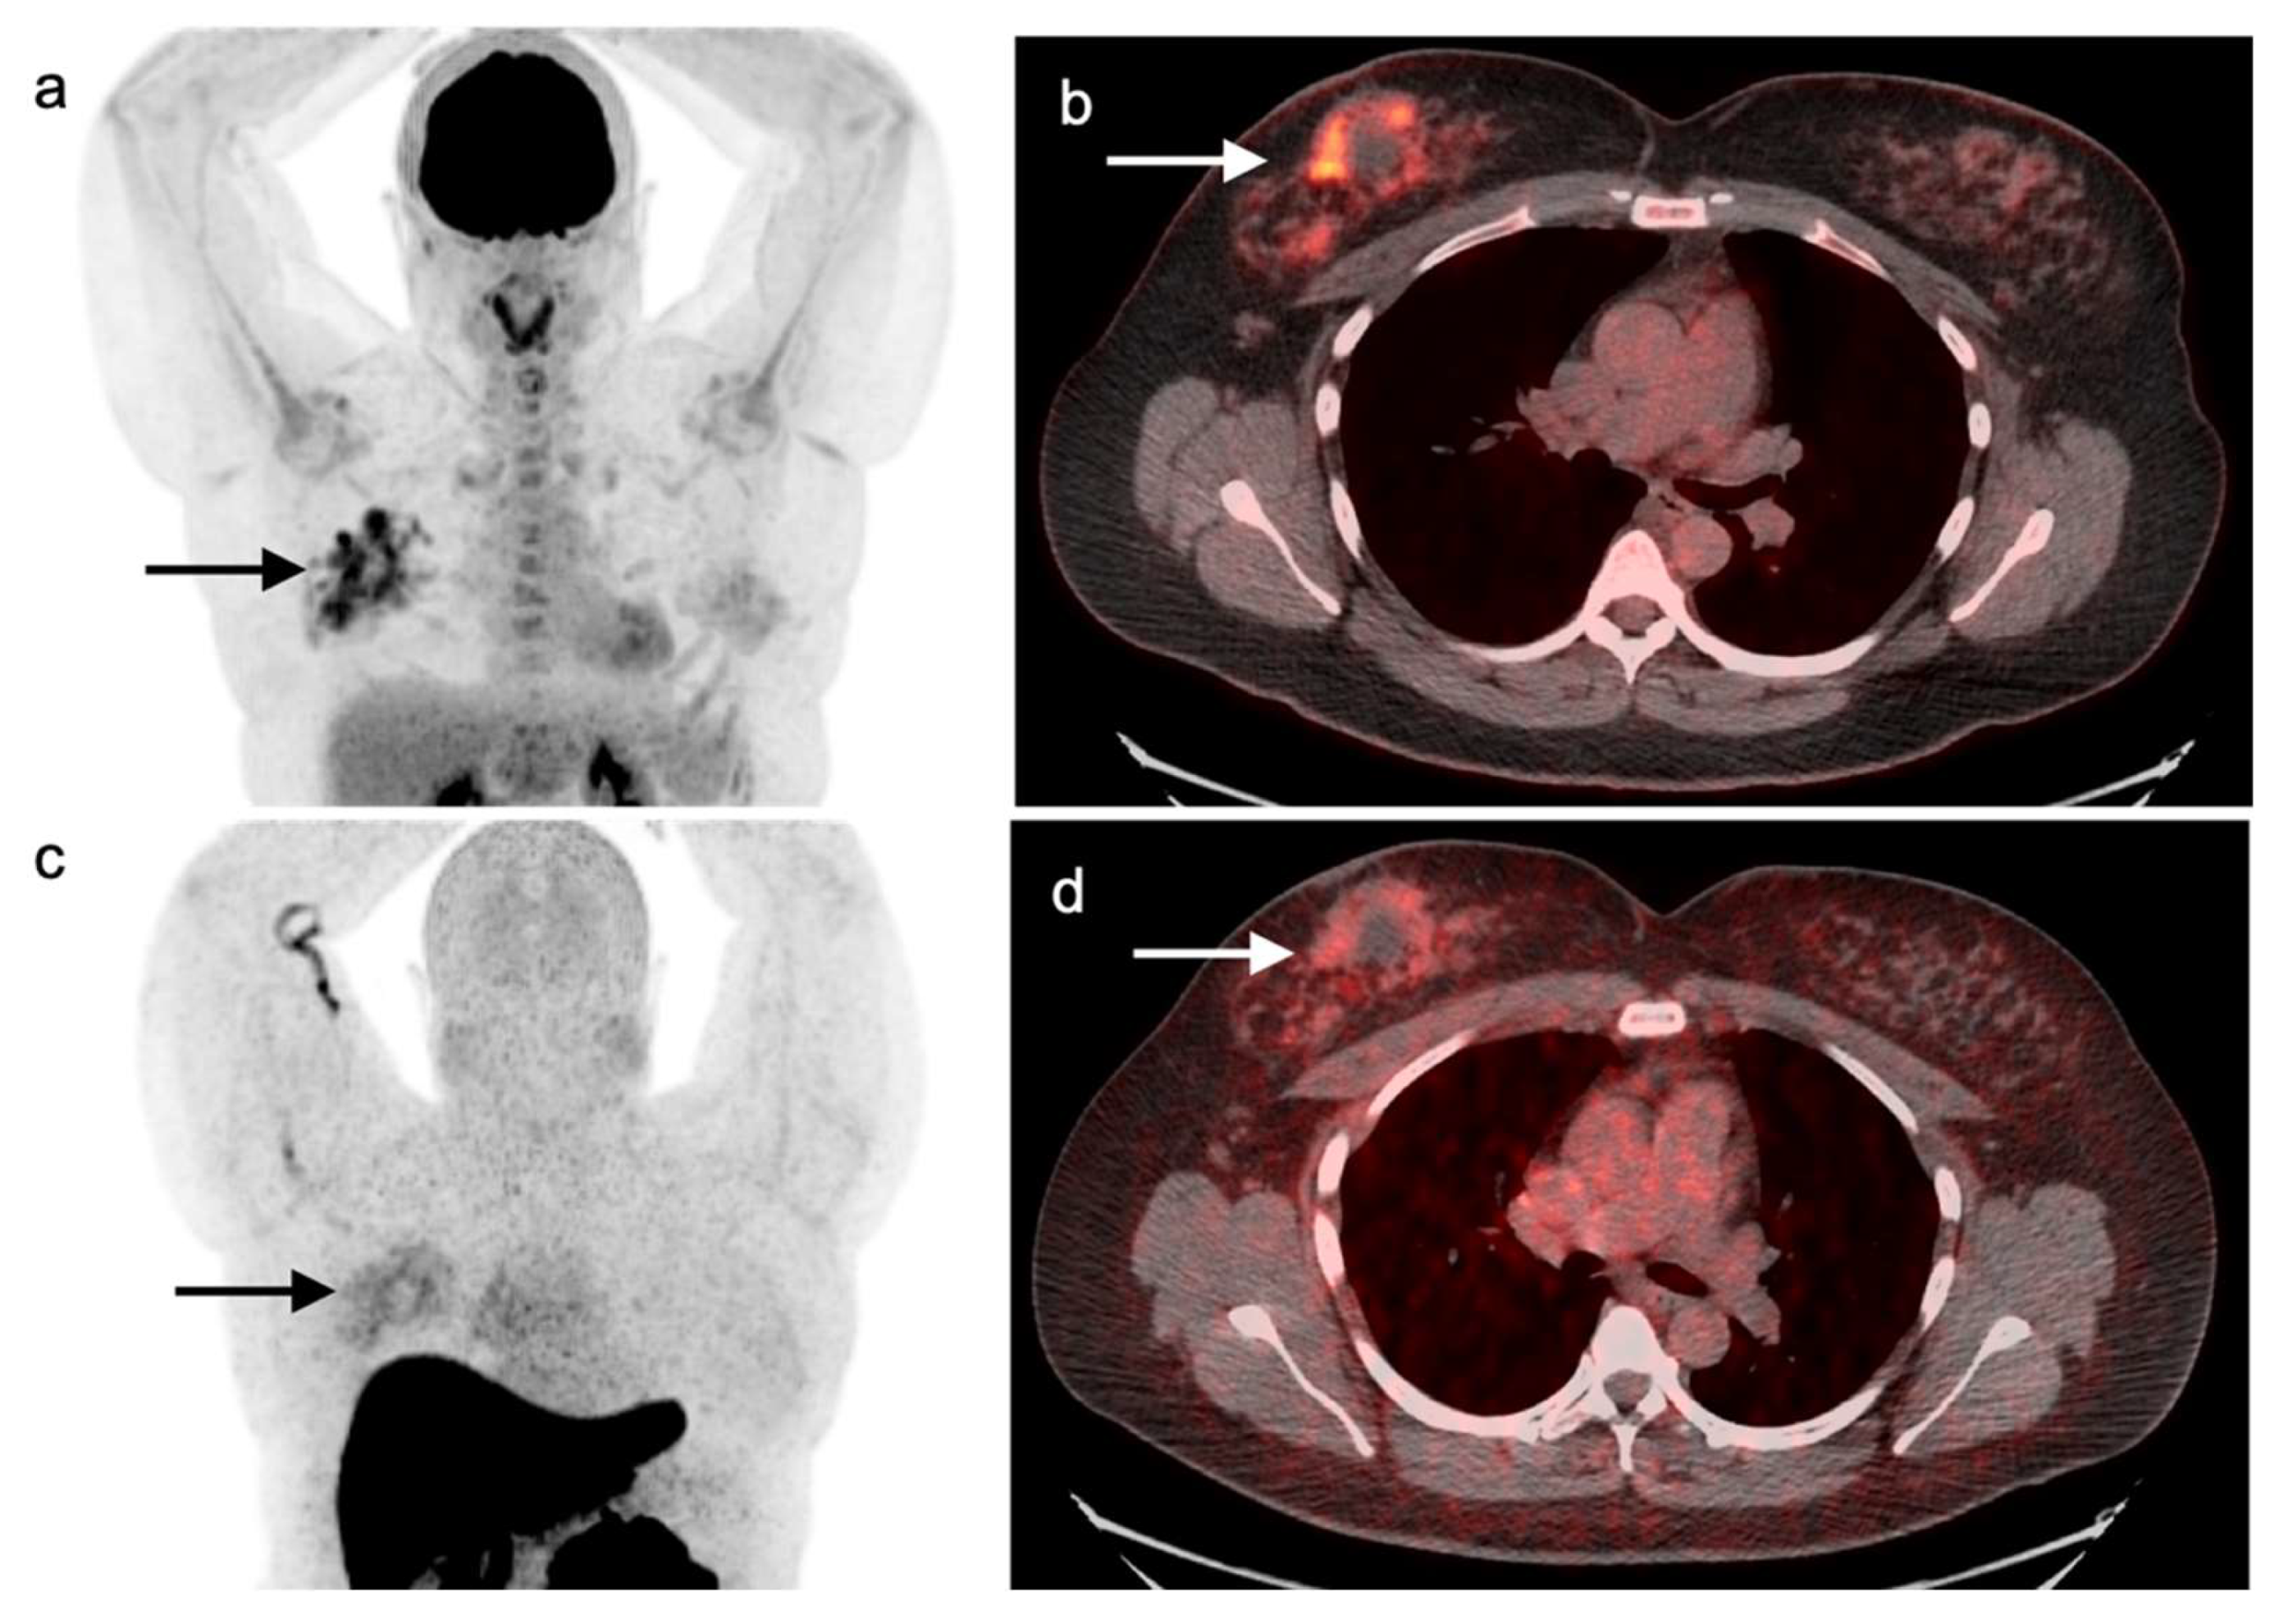

Immunotherapeutic approaches are becoming more common in the treatment of lung cancer, and include a variety of check-point inhibitors, such as PD-1 inhibitors (nivolumab, pembrolizumab, cemiplimab), PD-L1 inhibitors (atezolizumab, durvalumab), and the CTLA-4 inhibitor ipilimumab. These drugs may cause systemic inflammatory reactions, called immune-related adverse events (irAEs) with a variety of manifestations involving many organs and lymph nodes, including sarcoidosis-like reactions, and include a variety of imaging manifestations [8]. These inflammatory responses can mimic disease progression on FDG PET-CT [9]. In many cases, the immunotherapy, can be temporarily discontinued if the irAEs are producing clinically significant complications [10]. In these cases, an FDG PET-CT scan can be considering during the interval of discontinuation to differentiate irAEs from true progression. However, in some cases, a biopsy of target lesions identified by FDG PET-CT may be required to differentiate between irAEs and progressive cancer.

Post radiation changes present with findings involving anatomic structures with a geographically distinct margins (Figure 5). Accurate clinical history with awareness of the prior radiation field location is essential to avoid misdiagnoses. Procedures such as talc pleurodesis used for treatment of recurrent pleural effusions or pneumothorax can lead to chronic granulomatous inflammatory process with nodularity and associated calcifications along the pleural surfaces and can mimic malignant process [11]. This is typically strongly FDG-avid due to host reactive change. FDG embolus, a tiny hypermetabolic clot within the lung parenchyma without underlying CT correlate, is associated with technique during injection of tracer activity. Follow-up chest CT or attention to this specific finding on future studies would often resolve the diagnostic dilemma associated with this situation [12]. Iatrogenic or traumatic injury to the bones including procedures such as sternotomy or thoracotomy can present with increased FDG uptake at these sites due to the healing process. These conditions can be differentiated from malignancy in that the metabolic activity at these locations is shown to be lower than pathological fractures resulting from malignant processes, which has been found to be statistically significant. However, accurate clinical and surgical history, and careful attention to CT imaging is essential in evaluating FDG avid osseous lesions [13].